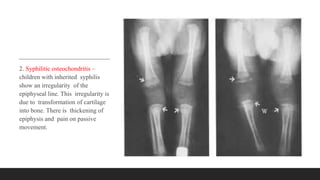

2. Syphilitic osteochondritis –

children with inherited syphilis

show an irregularity of the

epiphyseal line. This irregularity is

due to transformation of cartilage

into bone. There is thickening of

epiphysis and pain on passive

movement.